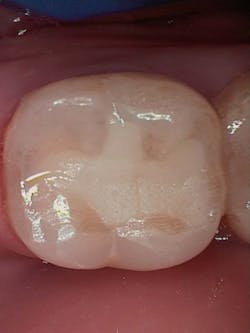

Figure 3 shows the final restoration immediately after placement. Figure 4 shows the final restoration of an initial caries lesion on the buccal. The clinician anticipated maturation of the glass-hybrid in choosing a lighter shade of A2, which initially appeared much too light. A slightly darker shade may have been more appropriate.